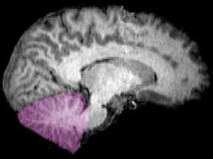

Las pruebas revelaron que a la joven le faltaba todo el cerebelo; y que en el espacio en el que este debía estar no había tejido alguno, sino líquido cefalorraquídeo, un líquido de color transparente que baña el encéfalo (región en la que se encuentra el cerebelo) y la médula espinal. Este líquido amortigua al cerebro y lo protege de enfermedades.

El cerebelo se encuentra debajo de los dos hemisferios cerebrales y está constituido por pliegues mucho más pequeños y compactos de tejido que el resto del cerebro. Representa alrededor del 10% del volumen total de este órgano, pero contiene el 50% de sus neuronas (unos 85.000 millones).